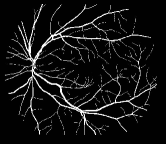

Refer to caption

Figure 1: Vessel segmentation results of side-output(s-out) layers produced by three networks. From top to bottom the network is normal DSN (with no short connections), BS-DSN (DSN with bottom-top short connections) and BTS-DSN (DSN with both bottom-top and top-bottom short connections), respectively.

As pointed out in recent works [15, 17], a good semantic segmentation network should learn multi-level features. Further, it should have multiple stages with different receptive fields to learn more inherent features from different scales. FCN, taken as an example, uses skip connections to fuse multiple stages outputs, as well as the HED network, in which a series of side-output layers are added after each stage in VGGNet. The HED network was first proposed for edge detection, and further used for image-level vessel segmentation in recent studies [6, 16], with significant performance. However, our experimental results show that such network architecture is not appropriate for vessel segmentation directly. Figure 1 provides such an illustration. Reasons for this phenomenon are straightforward. On one hand, the side-output of the first layer often contains too many noises. On the other hand, the features produced by the last side-output layer are too coarse due to information loss of pooling operation. Obviously, the inaccurate vessel map of side-output1 and side-output4 should have negative impacts on the final segmentation result.

In addition, we can observe from Figure 1 that the side-output1 and side-output4 of the BTS-DSN were more accurate compared with those of the DSN.